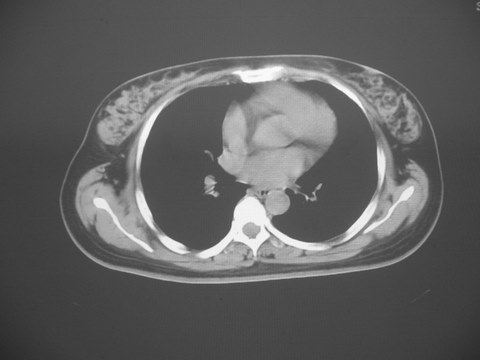

无意中发现右背部肩胛下缘半球状突起,无红,热,痛感觉。拍平片未见异常。ct发现右肩胛下角深层新月型软组织肿胀,ct值-50至15,大家看看是什么性质,来源,初步考虑来源于下后锯肿,考虑下后锯肌肿胀,可是病人无明确外伤史,也不疼痛

三、弹性纤维瘤影像

典型位于背部,在肩胛下角和胸壁软组织之间,肿瘤表面为菱形肌和背阔肌所被覆深部,紧邻肋骨和肋间肌,呈半圆形或扁豆状,宽基底与胸壁相交,边界比较清楚,相邻的肌肉和肋骨无侵蚀,部分病变与其表面的临近肌肉之间可受压呈弧形的脂肪界面,肿瘤周围软组织无水肿。

从mr表现可以推断ct影像,即肿块呈软组织密度,病灶内可出现脂肪密度的低密度影。